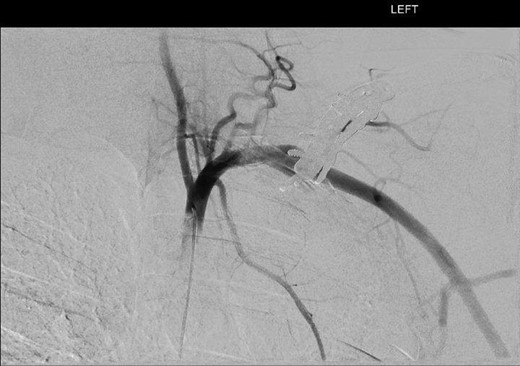

DSA oblique view illustrating fusiform left subclavian pseudoaneurysm.

Digital subtraction angiography via the right common femoral artery (CFA) was performed depicting fusiform aneurysmal dilatation of the mid left subclavian artery posterior to the clavicular plates and screws. Further, a focal area of irregularity was noted along the inferior aspect of the artery at the distal aspect of the aneurysm. On the dynamic study with arm in abduction there was significant compression of the artery by prominent clavicular screws at the site of the pseudoaneurysm.